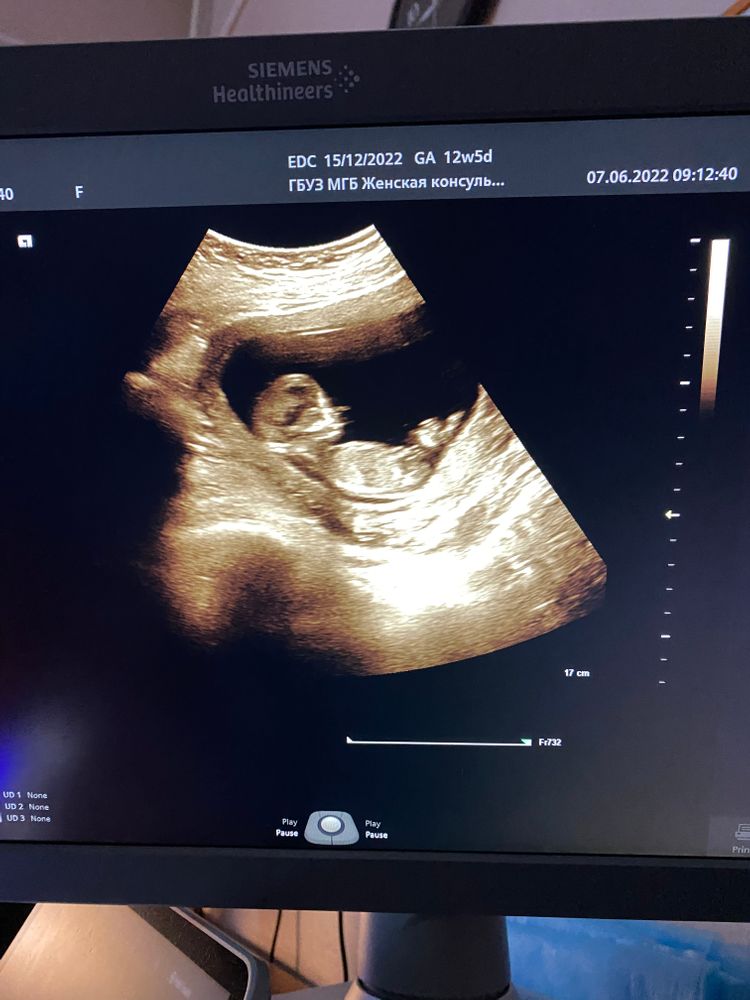

Первый скрининг

Изображение

Вот и прошел наш первый скрининг,по результату узи все в норме,по размерам мы опережаем срок на неделю,пол конечно не увидели,да она и не хотела этого делать,во